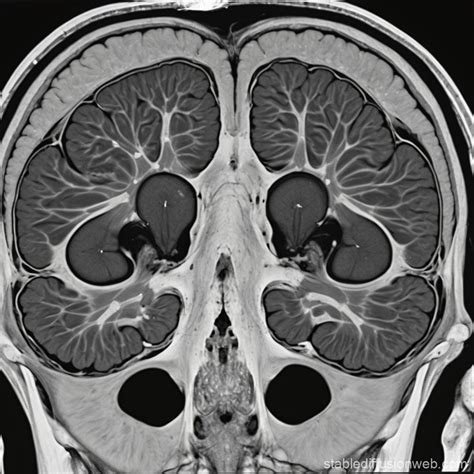

The primary purpose of using a contrast agent during a Computed Tomography (CT) scan is to make specific areas "pop" on the monitor. Without contrast, some organs—like those in the abdomen—might look similar in density, making it difficult to spot subtle abnormalities. When the Ct Contrast agent, which often contains iodine or barium, enters your system, it absorbs X-rays differently than the surrounding tissue. This interaction creates a distinct visual difference in the final image, effectively "highlighting" the targeted area.

• Intravenous (IV) Injection: This is the most common method. The dye is injected into a vein in your arm or hand, allowing it to circulate through your bloodstream to highlight blood vessels, the heart, the liver, or the kidneys.